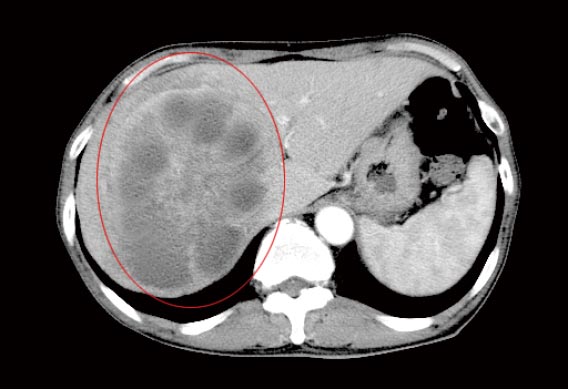

治療前のCT検査結果

肝臓の右側(右葉という区域)に大きく広がる転移性のがん病巣が認められました。